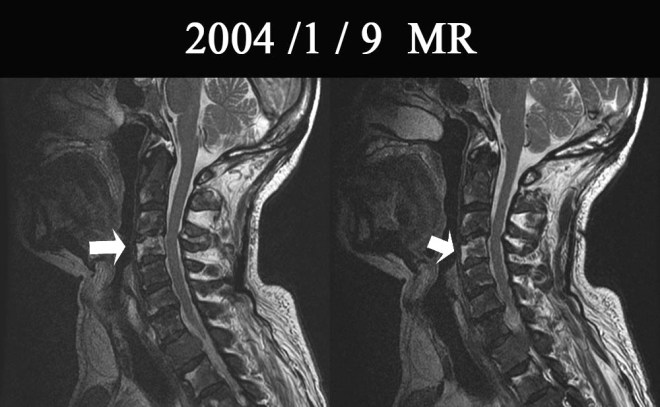

캡처.JPG

환자 분은 2002년 전립선암 발견 시부터 총 4회에 걸쳐서 방사선 치료를 흉추와 요추 골반 등에 보이는 전이된 종양 부위에 받았다.

위에서 보듯이  2003년 12월 24일 사진에서 전신에 뼈전이가 되어 있는 것을 알 수가 있다. 마지막 방사선 치료를 2003년 12월부터 2004년 1월까지 환자는 받았다.

1-2.jpg

위의 사진은 2004년 1월 방사선 치료를 마쳤을 때의 MR 사진이다. 화살표의 하얀 부분은 정상뼈이다. 나머지 검은 척추뼈는 모두 암의 전이로 인하여서 검게 보여지는 부분이다. 하얀 부분 외에는 거의 남아 있지 않을 정도로 전 척추뼈에 암이 전이가 되어 있었다.